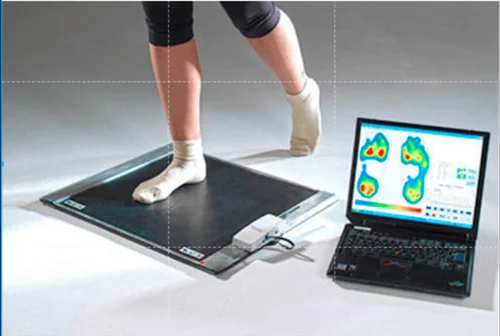

3D Foot Scanning & Analysis

Our advanced 3D scanning captures every contour of your foot for a highly accurate assessment. Custom Orthotic Insoles

Precision

Measures arch height, pressure points, and gait.

Early detection of pressure zones prevents ulcers in diabetic feet.